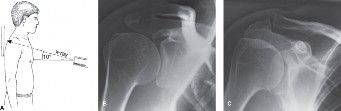

The correct answer is (C). Each RC tendon has specific tests for pathology. The supraspinatus strength test (aka Jobe test) is performed by abducting the shoulder to

90 degrees, bringing the arm in the scapular plane (30 degrees forward), and maximally internally rotating the arm (thumb pointing to the floor) (Fig. 2–1). The test is positive if weakness is found or if pain is experienced. Another test for the supraspinatus is the drop arm test. In the drop arm test, the arm is passively elevated by the examiner to the Jobe position, the patient is asked to attempt to keep it there, and the arm is released by the examiner. The test is positive if the patient is not able to keep the arm elevated and the arm drops.

Figure 2–1 Jobe test.

The belly press test (Answer A) and lift off test (Answer D) are used to evaluate for subscapularis pathology (Figs. 2–3 and 2–4). The hornblower test (Answer B) assesses the teres minor (Fig. 2–2). The external rotation lag test (Answer E) evaluates the infraspinatus.